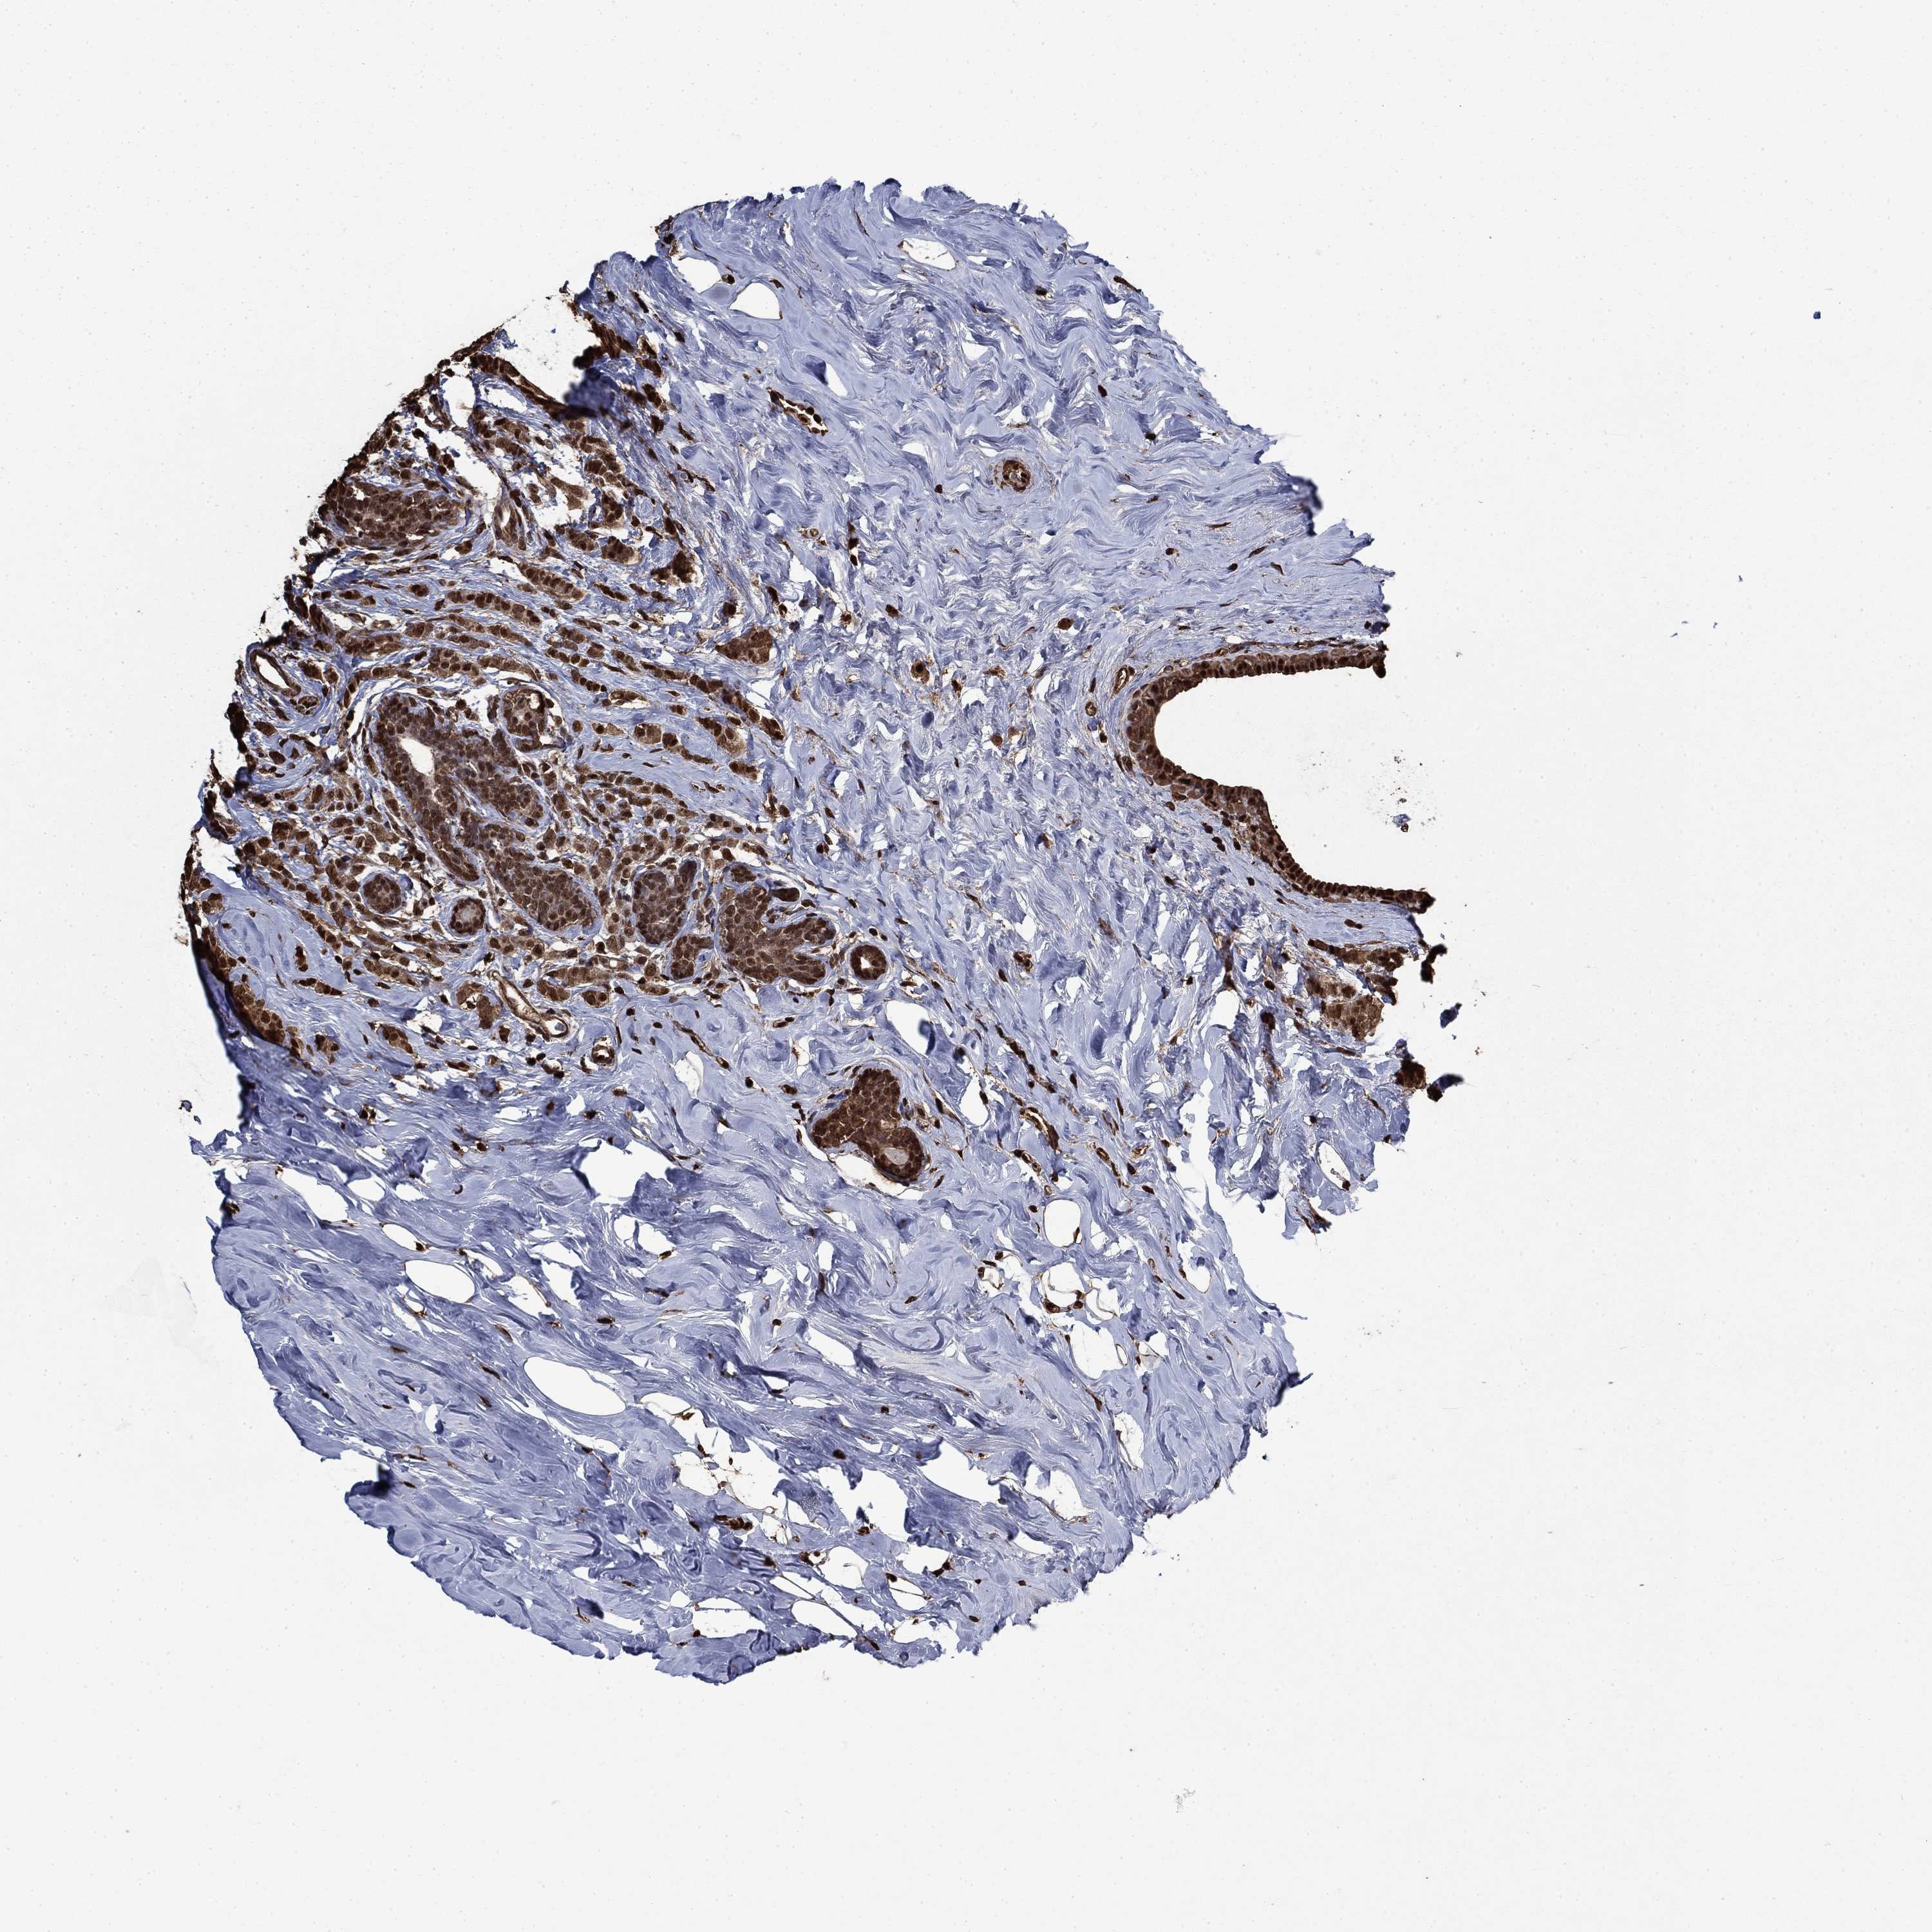

BRCA TCGA BRCA VALIDATION PROTEIN EXPRESSION

ANTIBODIES

AND

VALIDATION